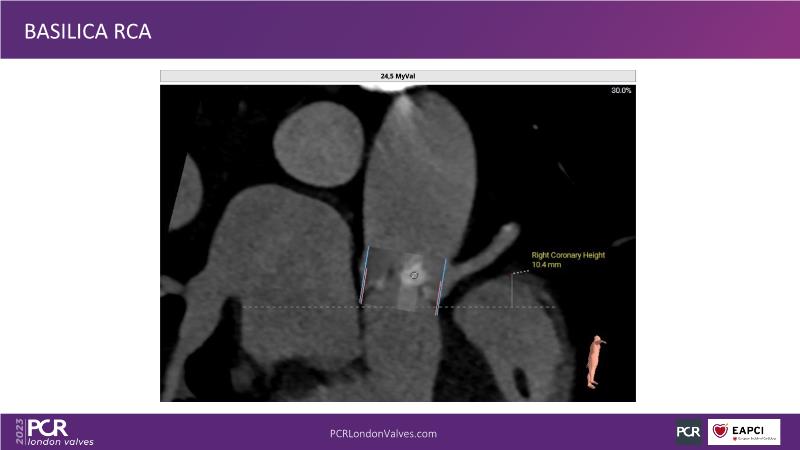

- To learn tips and tricks for managing bicuspid and valve-in-valve interventions